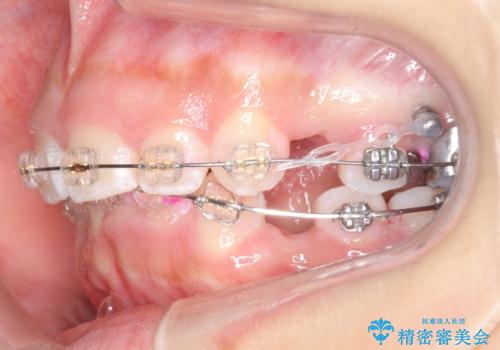

- 矯正装置

- プラスチックブラケット

奥歯のかみ合わせもずれていたため、上の奥歯を後ろに下げる処置をミニスクリューを用いて行いました。